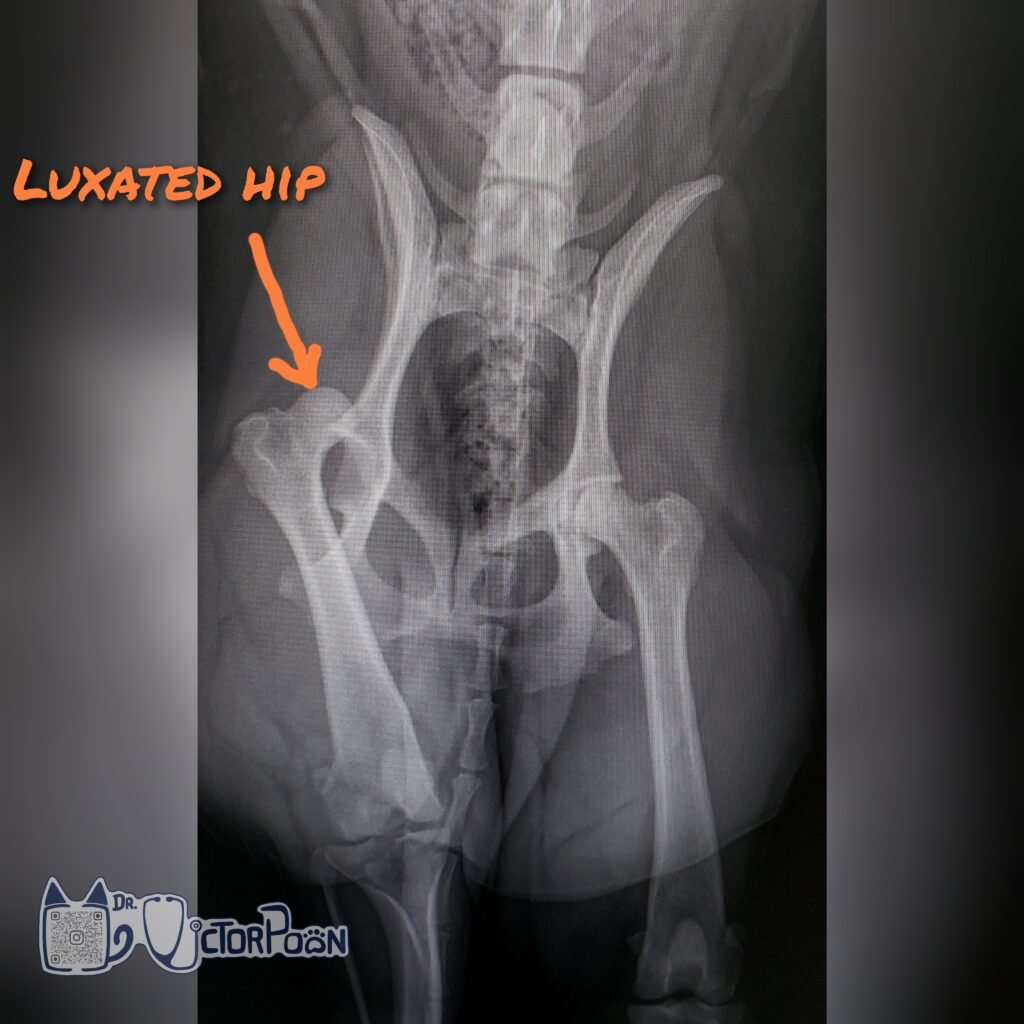

Surgical options should be considered for chronic hip luxation and hips that reluxate after closed reduction. The 2 main types of procedure include round ligament reconstruction (Toggle Pin technique) and salvage procedures (femoral head and neck excision [FHNE] or Total hip replacement [THR]). Each procedures have their pros/cons, and should be discussed prior to surgical intervention.

Some of the factors for consideration include: Clinical signs, Weight and size, Age, Cost and Hip conformation.